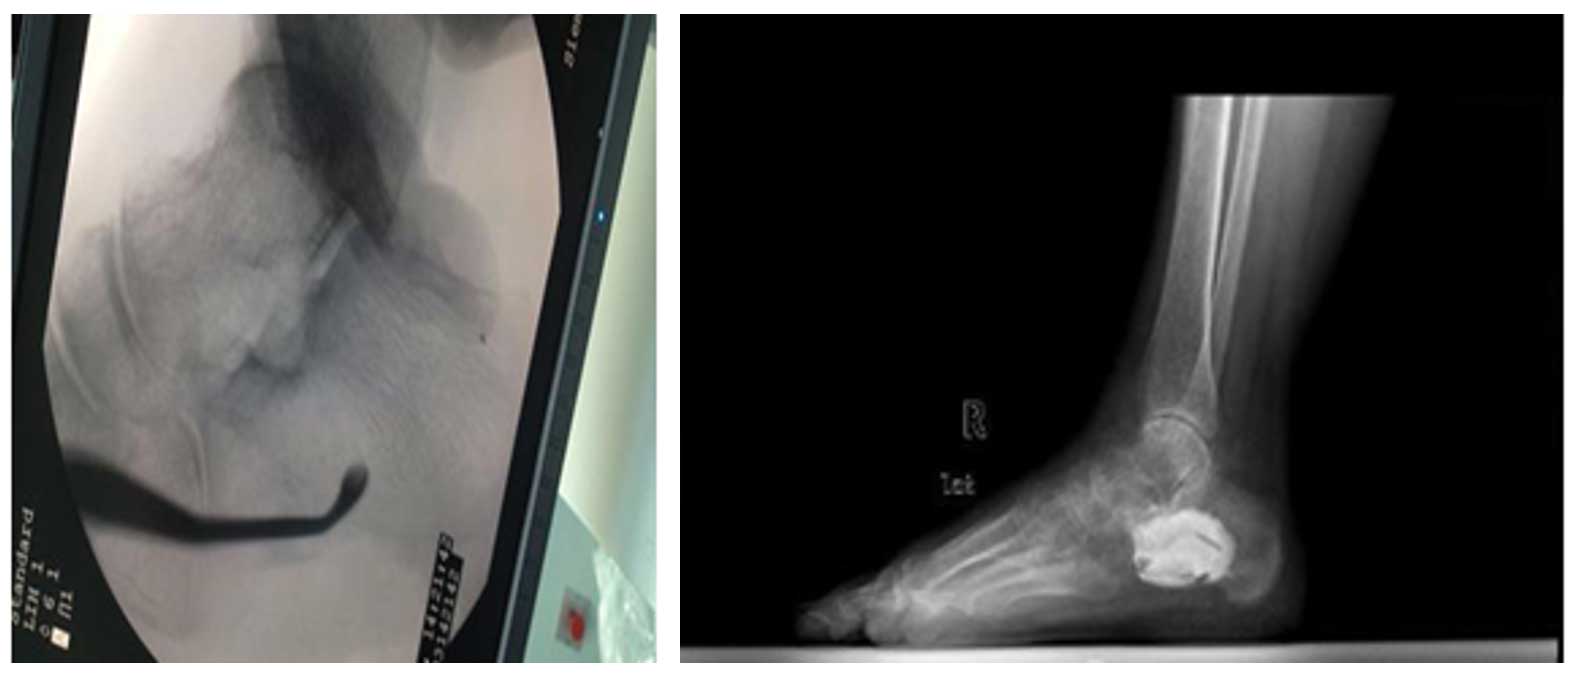

Ameliyat Öncesi: Röntgende sağ topuk kemiğinde yeniklik, MR’da aynı bölgede tümör dokusu görülmekte.

Ameliyat Esnası ve Sonrası: Skopi’de Küret yardımı ile tümörün temizlenmesi ve röntgende oluşan boşluğun kemik çimentosu ile doldurulması görülmekte.